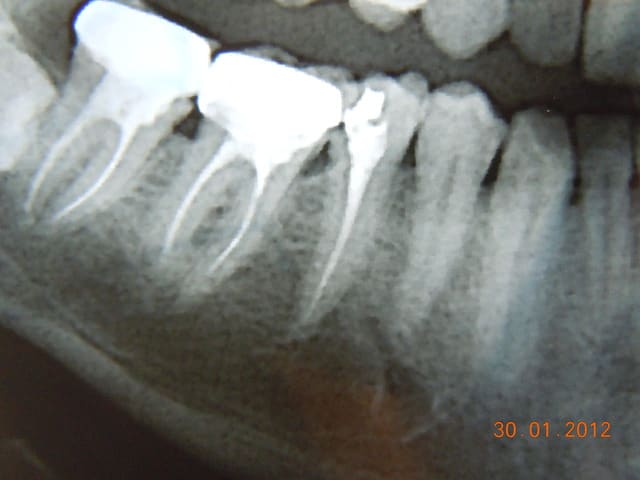

eMax de ce soir.

Collage automordançant G-Cem.

Bah voilà un argument de plus pour la levée de l'opposabilité pour les composites. Alors ameli? Qu'est qui favorise le plus l'accès au soins? Cet onaly qui doit coûter entre 300 et 500€ ou un compo à 150€ qui, collé dans les même conditions, aurait un pronostic équivalent?

Je trouve que c'est un patient qui devrait avoir des soins paro et des compo, pas des e-max. Et j'aime pas le collage au G-cem, en fait c'est le point faible de ton traitement, et c'est si facile de coller ce cas avec le total etch.

On peut penser qu'Arnaud aura vu le tartre sous-gingival et fait le nécessaire, mais pourquoi pas d'emax et plutôt des compos? Rapport à la taille des cavités? A l'hygiène pas top?

Oui rapport à la taille de la cavité. J'ai pas dit que c'était moins bien de faire un emax plutôt qu'un compo, je dis juste que c'est plus coûteux pour un bénéfice médical proche de zéro. Mais évidement si on veut faire un compo qui peut rivaliser avec cet onlay il faudra palper un pru plus que 28,92.

Il y a une équivalence thérapeutique entre les deux solutions tant que la forme de la préparation ne nécessite pas de délabrement, et bien que l'arsenal à mettre en œuvre est bien plus important pour l'inlay, je préfère de l'eMax dans ma bouche (et un peu de joint résine) qu'un compo.